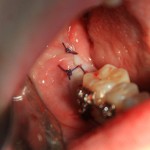

Все. зуб удален. Осталось наложить швы. Лунка зуба зашивается наглухо:

Делаем контрольный снимок, чтобы убедиться в том, что мы не повредили семерку: